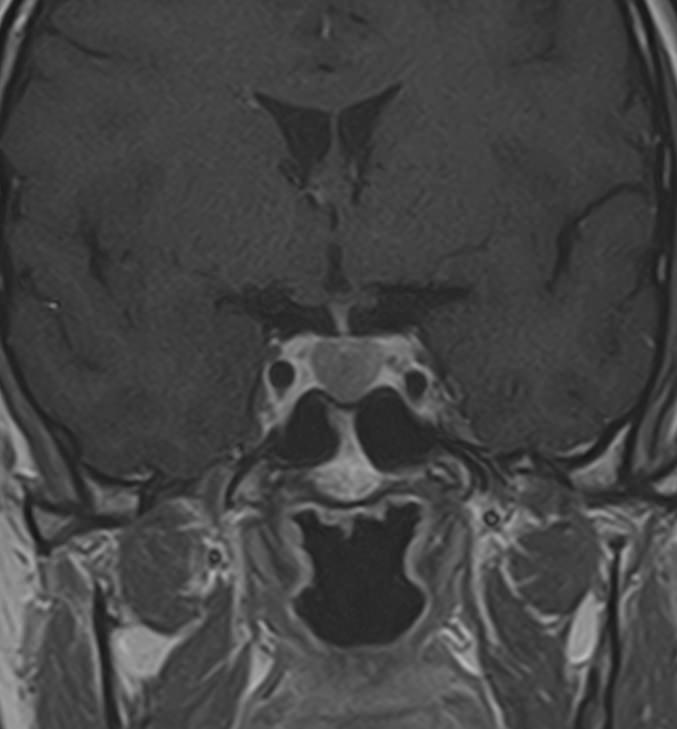

Для выявления опухолевых образований гипофиза проводится МРТ гипофиза с контрастным усилением. Для этого пациенту внутривенно вводится препарат, содержащий контрастное вещество, имеющее в своем составе металл гадолиний. Контрастное вещество избирательно накапливается в патологических очагах, интенсивность этого накопления можно оценить визуально, а также с помощью компьютерной программы — в цифровом выражении.

Метод позволяет создавать детализированные изображения области турецкого седла и является лучшим способом диагностики любых объемных образований гипофиза. С помощью МРТ гипофиза можно выявить макроаденомы и большинство микроаденом гипофиза размером от 1 мм.

В клинике «Доступная медицина» проводится МРТ гипофиза с контрастом на современном высокопольном томографе TOSHIBA VANTAGE TITAN 1,5 Тесла. Индукция магнитного поля 1,5 Тесла обеспечивает высокую четкость изображения и отвечает мировым стандартам качества диагностики заболеваний центральной нервной системы.